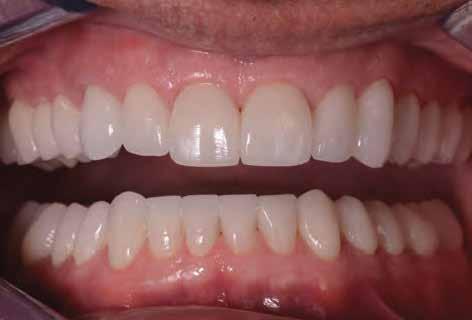

Az extrahálás és az új mosoly

A fogak extrahálása és az alveoláris plasztika teljes narkózis mellett történt meg, így teremtve ideális helyzetet a protetikai ellátáshoz. A műtéti beavatkozás után a páciens az ideglenes fogsorral távozott. Egy héttel később jött kontrollra. Nemcsak látványra változott meg nagymértékben, hanem egyértelműen magabiztosabb és önbizalommal teli volt a fellépése (12. ábra)

Összegzés

Az elsődleges terápiás szakasz kulcsfontosságú volt a teljes rehabilitáció szempontjából. A páciensnek nem csak szép, esztétikus mosolyt kölcsönzött, hanem életminőségének javulását is hozta (13. ábra). A Digital Denture folyamatnak köszönhetően a kezelés ráfordításai is alacsonyak voltak. A fiatal nő messzemenően boldog, magabiztos és motivált a következő lépéshez.

12. ábra: Páciensünk egy héttel fogainak extrahálása és az ideglenes fogsor azonnali behelyezése után. 13. a–d ábrák: Látványos átalakulás: kezelés előtt és után. A páciens maga hangsúlyozta ki életminőségének jelentős javulását.